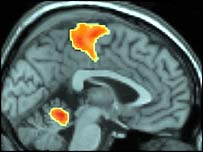

Đây là hình chụp não khi phụ nữ thật sự đạt đỉnh: não gần như không hoạt động

Lý do là vì trong cơn cực khoái thật sự, vùng vỏ não, điều khiển phần ý thức của não, đóng lại hoàn toàn.

Còn khi giả vờ, vùng vỏ não vẫn mở.

Máy scan cho thấy trong lúc hoạt động tình dục, những phần trong não phụ nữ có tác dụng kiểm soát nỗi sợ, lo lắng và tình cảm bắt đầu thư giãn và giảm hoạt động. Nó đạt tới đỉnh khi cực khoái, khi mà các trung tâm tình cảm trong não phụ nữ đóng hẳn lại.

"Điều chính mà chúng tôi thấy ở người phụ nữ là sự ngưng kích hoạt ở não, rất rõ rệt và không thể tin được. Đây là kết quả chính của nghiên cứu. Ta thấy có sự ngưng kích hoạt ở nhiều phần trong não, đặc biệt là ở khu vực kiểm soát tình cảm và sợ hãi."

"Phụ nữ có thể giả vờ rất khéo là họ đạt đỉnh điểm, nhưng trong não thì khác. Việc ngưng kích hoạt các phần trong não có lẽ là yếu tố quan trọng nhất để đạt cực khoái."